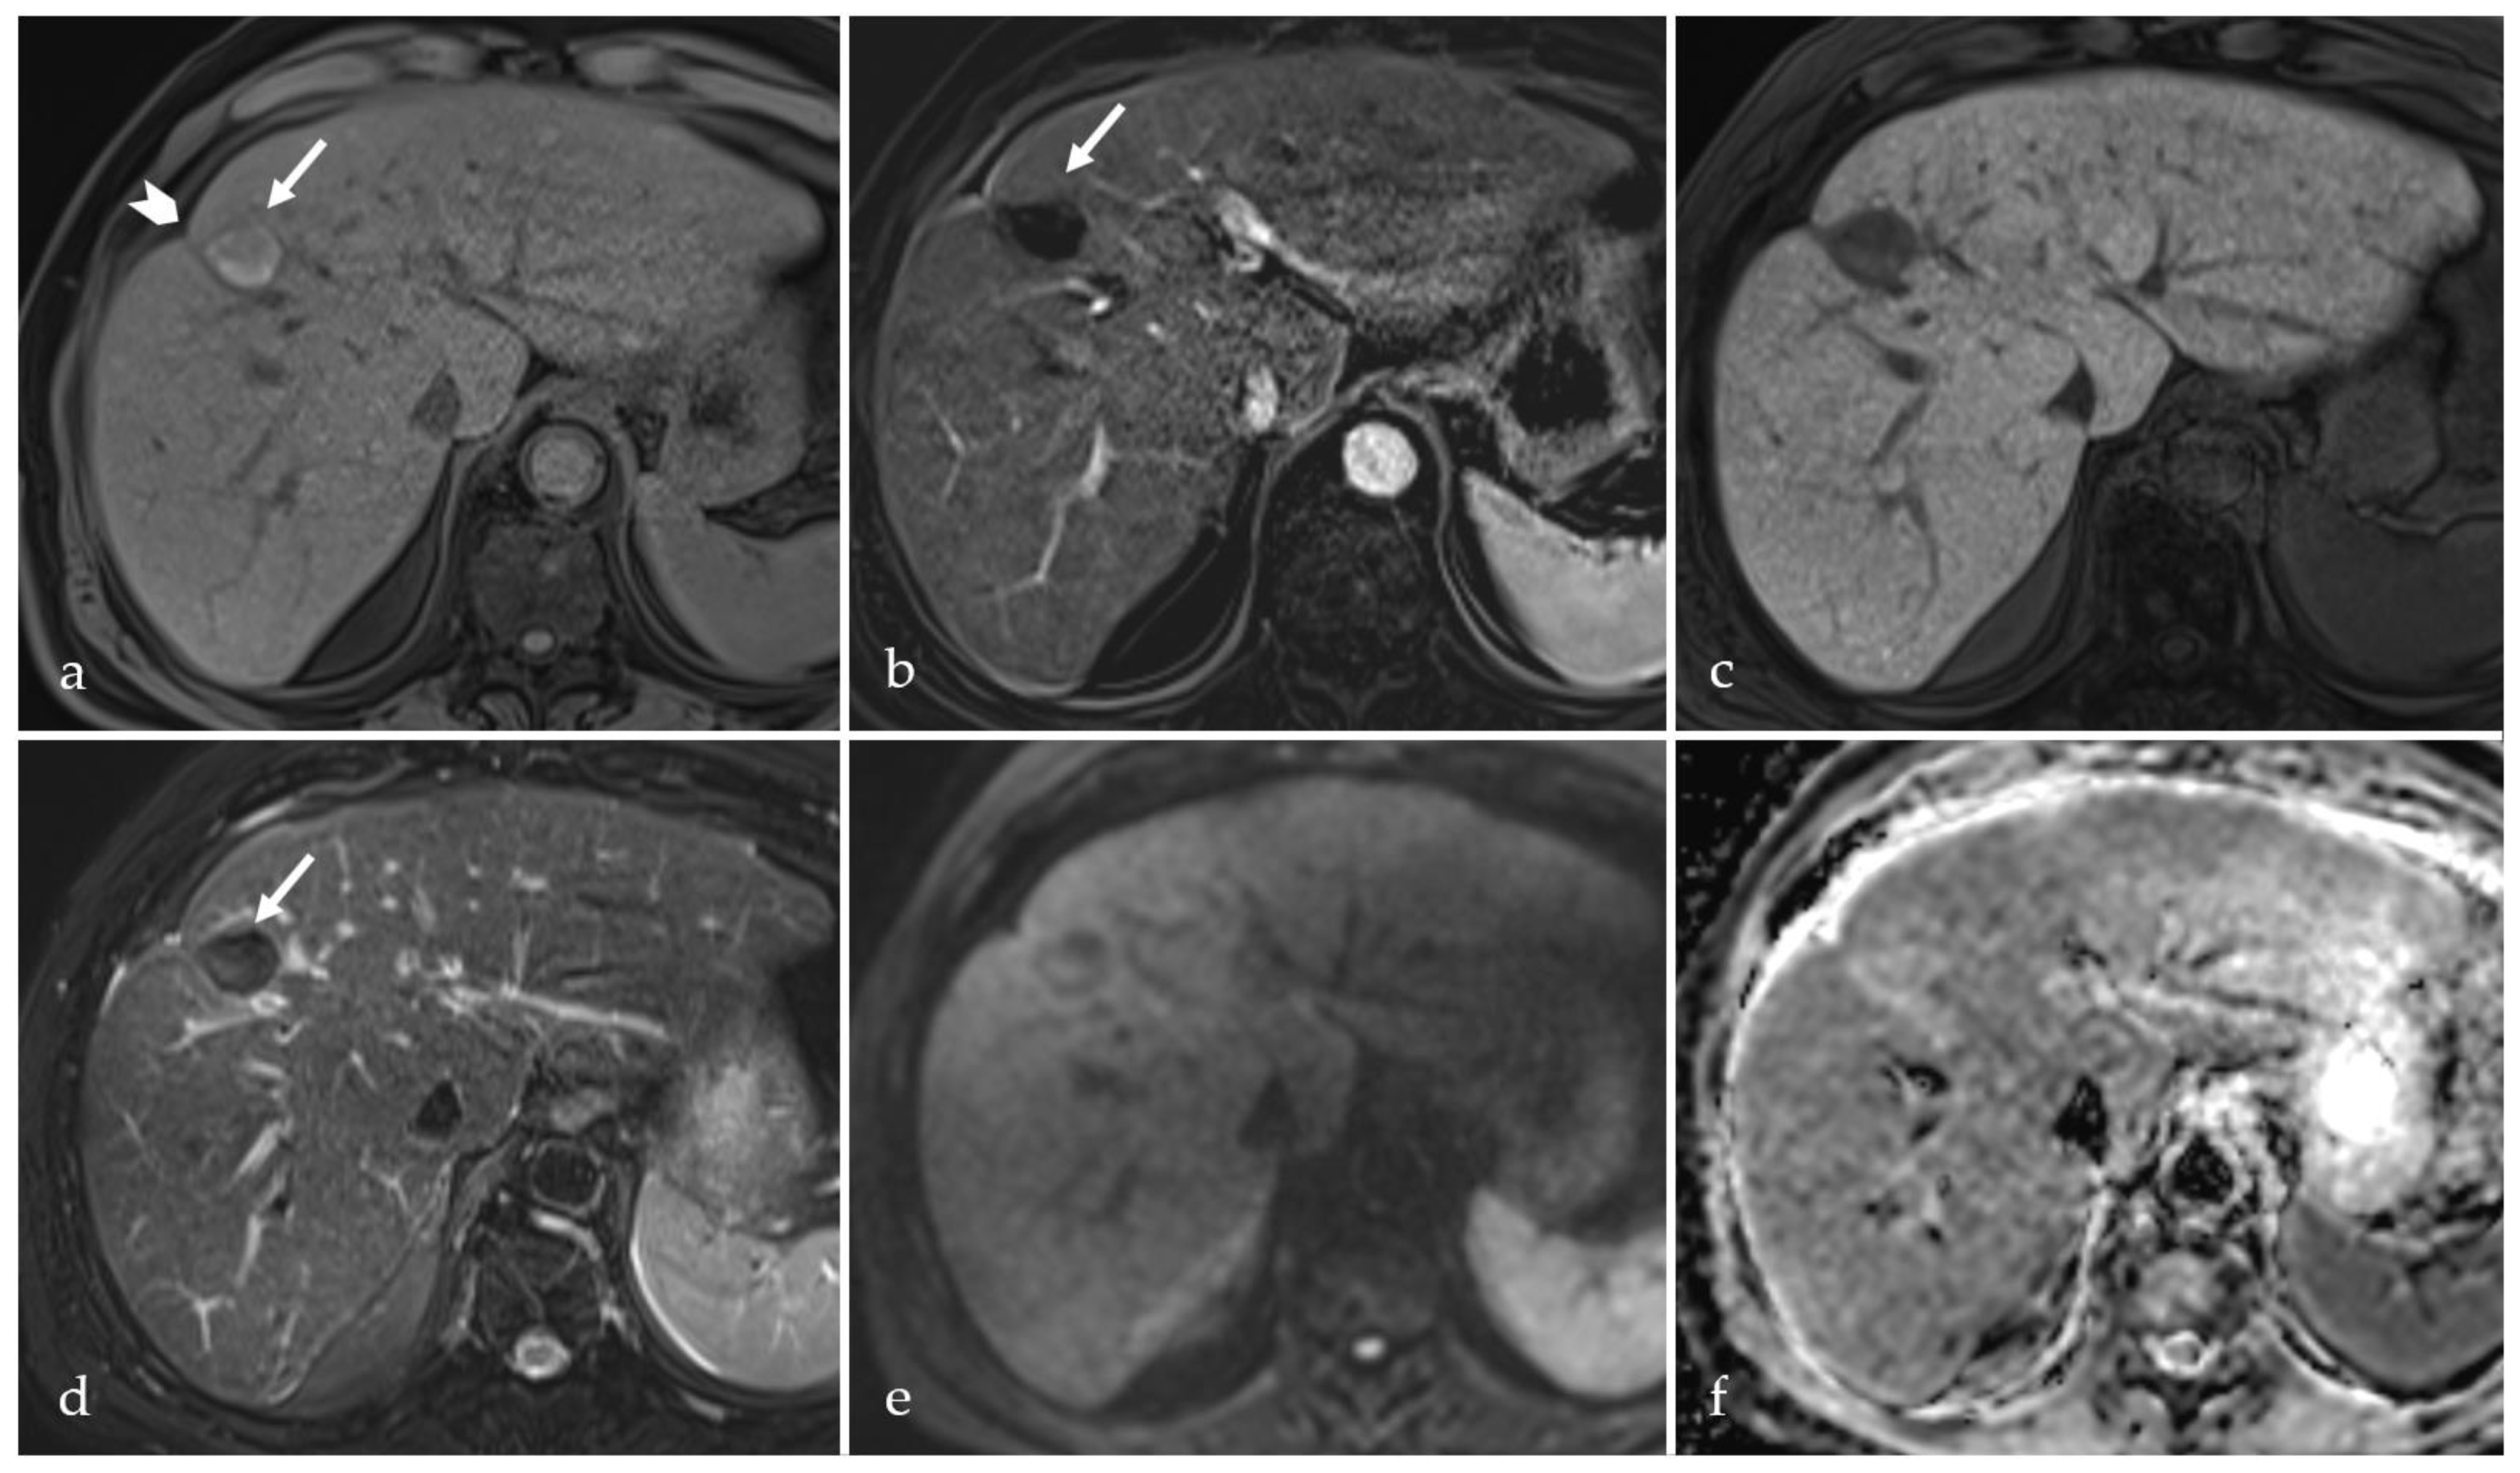

3.2. Expected Post-Treatment Imaging Features in the Absence of Viable Tumor Tissue

3.3. Transient Hyperemia